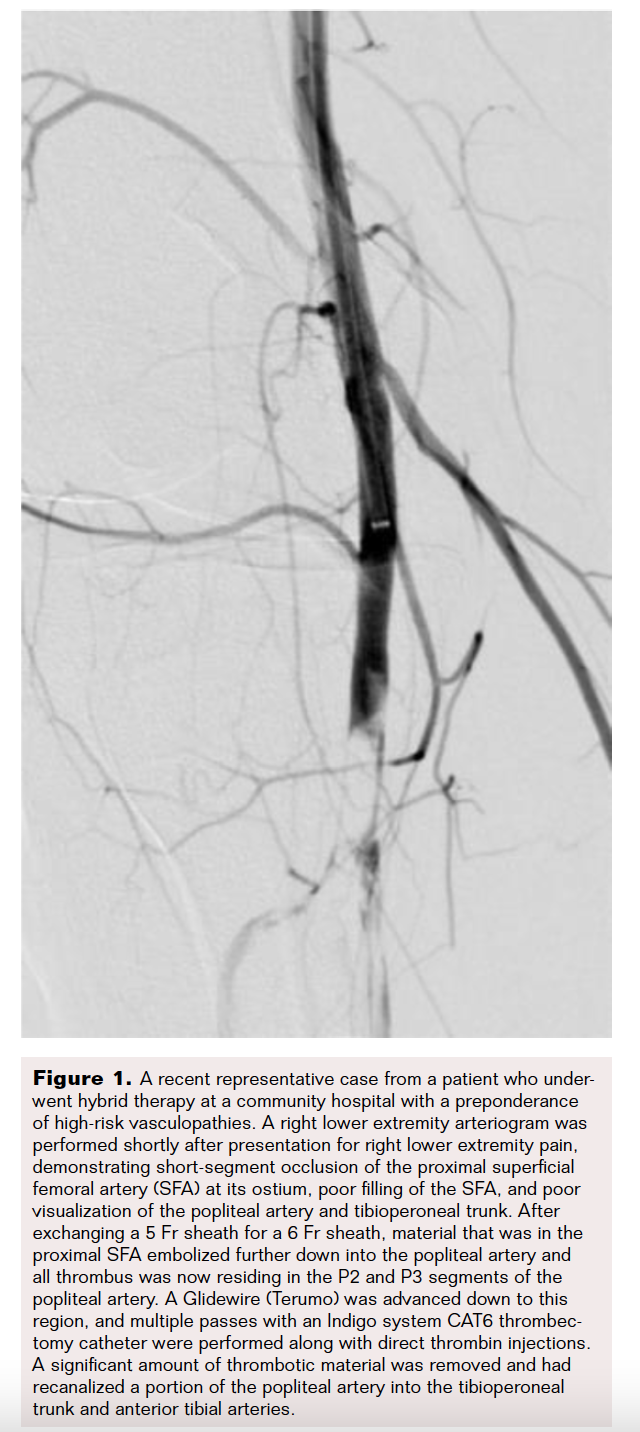

Early recanalization following vessel occlusion has been associated with improved clinical outcomes in ALI. Introducing hybrid therapy with the Indigo system in addition to CDT was intended to improve patient outcomes in a community hospital with a preponderance of high risk vasculopathies (Figure 1 and Figure 2).

Following the start of this initiative, CDT alone was associated with a longer, more tumultuous recovery. Hybrid therapy demonstrated improved clinical outcomes with significant improvements in time until return of pulses and decreased time from procedure to symptom improvement (Figure 3). Although there was a slight improvement in length of hospital stay, it was marginal in comparison; this could be due to confounding factors increasing hospital stay. Factors could include a secondary diagnosis such as pre-existing cardiovascular or cerebrovascular disease, hospital-acquired infection, or placement into rehab.